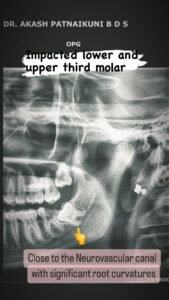

⦿ Oral Surgeries (Specialist/ Consultant)

. Surgical removal of impacted/ unerruped tooth.